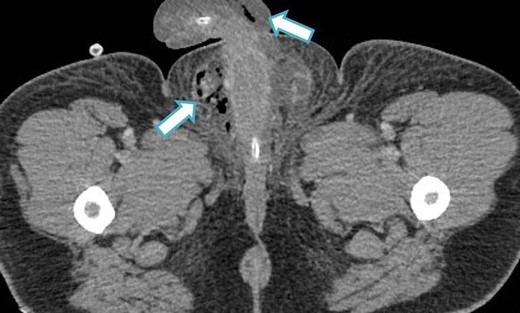

An urgent scrotal ultrasound demonstrated evidence of gas within the deep tissues of the scrotum but no abscess as shown in Fig. 1. Subsequently an abdomino-pelvic CT scan revealed multi-loculated collections in the right iliac fossa, suggesting perforated appendicitis with secondary extension of gas down the spermatic cord into the scrotum, as shown in Figs 2 and 3.

CT image (axial slice) showing gas within the scrotum and penile shaft.